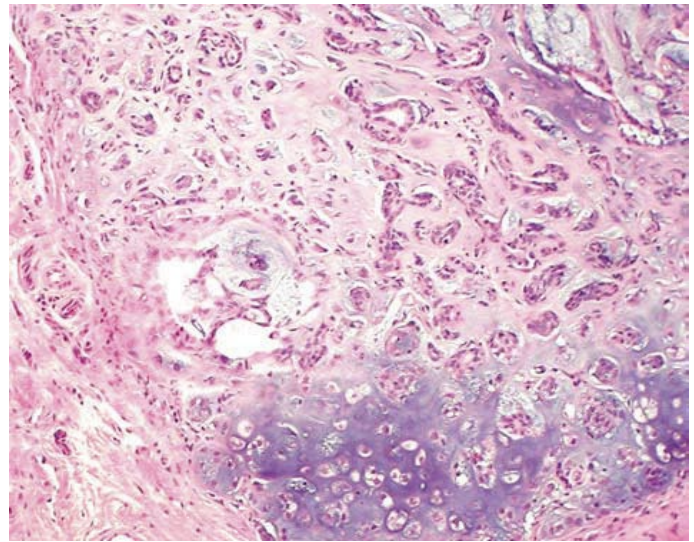

์ผ์ชฝ์ fibroma, ์ค๋ฅธ์ชฝ์ fibrosarcoma

- ex) fibroma: fibroblast orgin์ ์์ฑ ์ข